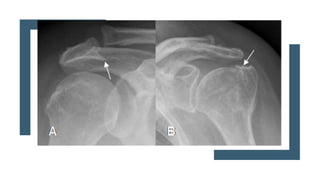

Radiológico

 AP

 Escapula en Y

 Outlet